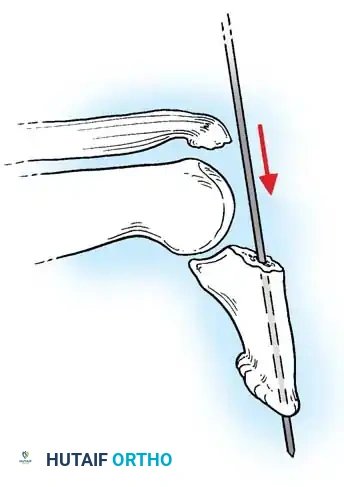

For intraarticular fractures involving more than one-third of the joint surface with associated subluxation, open reduction utilizing a pull-out wire and a transarticular K-wire is the gold standard.

Doyle Technique: Open Reduction and Fixation with Pull-out Wire

Indications: Displaced Type 4 mallet fractures, large avulsion fractures of the DIP joint.

Step-by-Step Surgical Procedure:

1. Exposure: Under tourniquet control and appropriate anesthesia, expose the DIP joint through a dorsal zigzag (Bruner-type) or H-shaped incision to prevent scar contracture over the joint.

INTRAARTICULAR FRACTURES Surgical Diagram

1. Distal Wire Placement: Isolate the distal phalanx. Pass a 0.035-inch (0.9 mm) K-wire longitudinally through the center of the distal phalanx, exiting the distal tip of the finger.

1. Reduction: Anatomically reduce the DIP joint. Carefully manipulate the dorsal articular fracture fragment into its anatomical bed using a dental pick or fine periosteal elevator.

2. Transarticular Fixation: Once the joint is reduced and held in full extension, drive the previously placed K-wire proximally across the DIP joint into the middle phalanx to secure the joint in extension. Verify the reduction and joint congruity with multi-planar fluoroscopy.